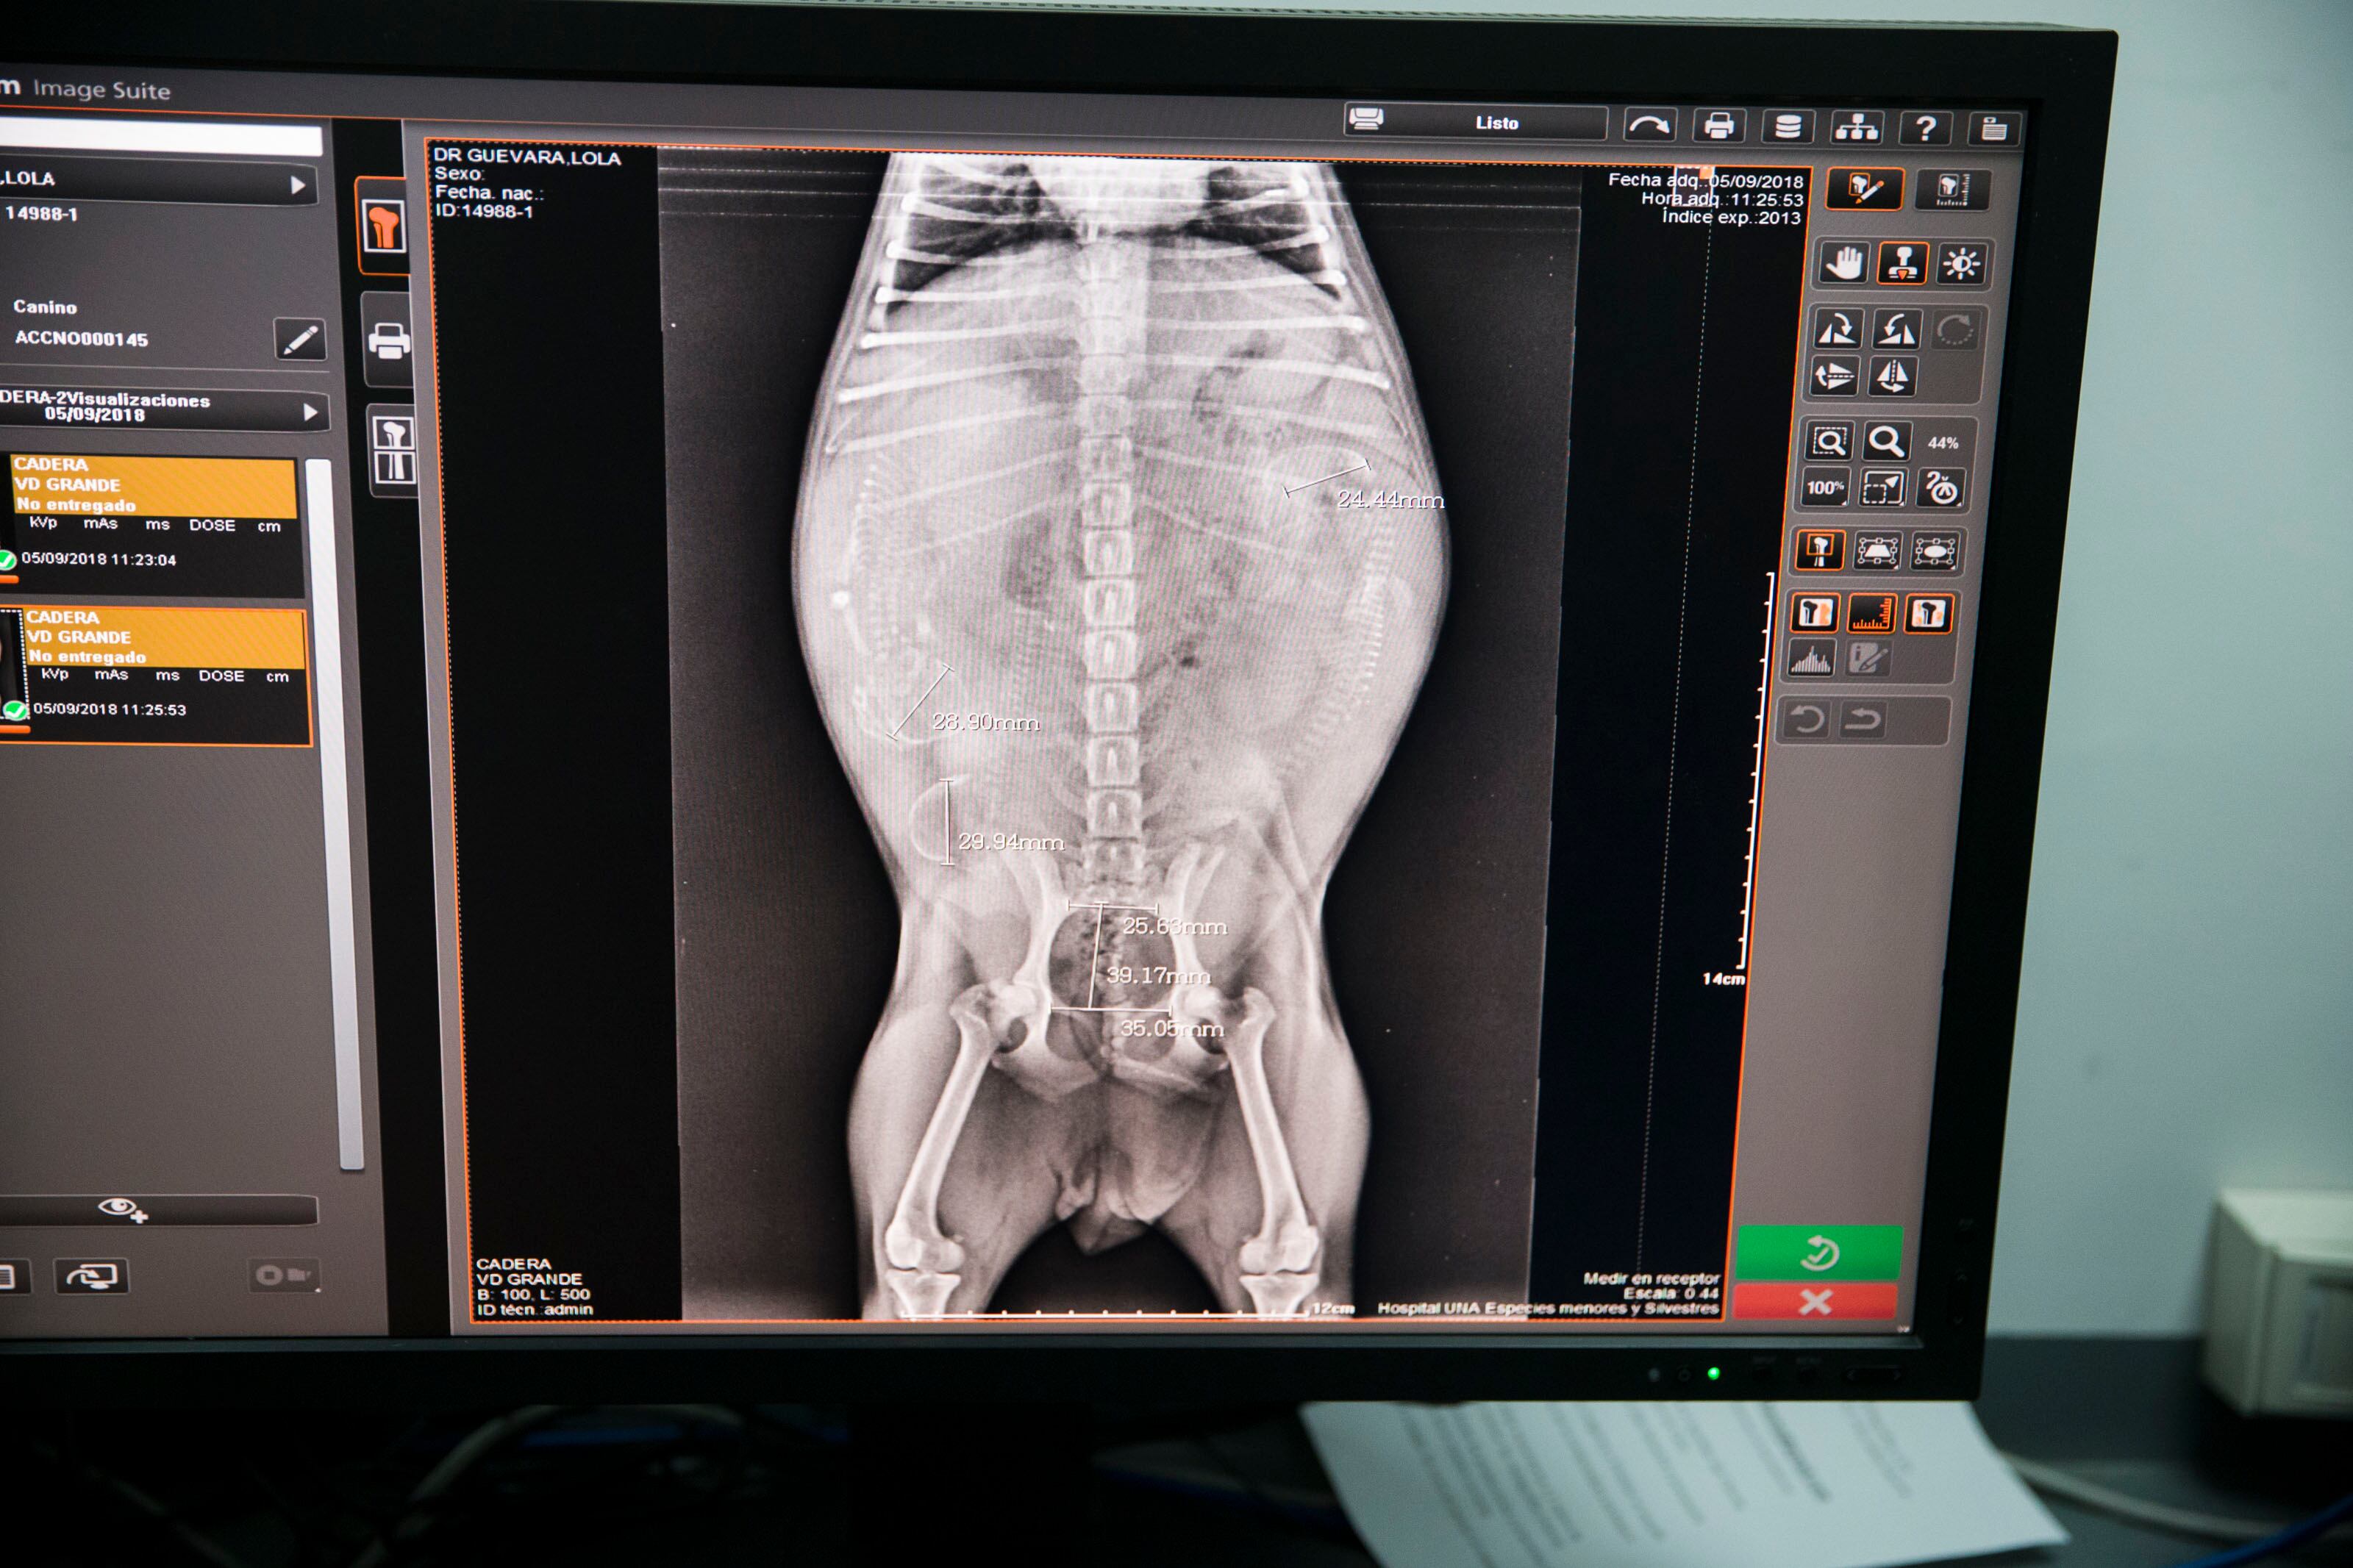

La doctora Isabel Hagnauer, del Hospital de especies menores, ve la parte de oftalmología veterinaria. Ella no cuenta con una especialidad en esa área, sin embargo, la trabaja por experiencia y afinidad. El miércoles 5 de setiembre ella atendió a Lola, una perra sin raza definida a quien le querían descartar úlceras corneales y ver si tenía disminución en la producción de la lágrima. Para suerte de Lola, después de los exámenes se determinó que estaba bien.

Aunque también acuden mucho a neurología. Ese fue el caso de Jira, una perra que tiene mucho dolor y por las posiciones en las que pone las patas fue evidente para el doctor Jiménez que lo que pasa con ella es un mal neurológico y no ortopédico.

Una de las pruebas que el veterinario le hizo al animal fue estriparle los deditos de la pata para ver si había sensibilidad, en el caso de ella el panorama estaba complicado. Luego de aplicarle una inyección contra el dolor, se le iban a revisar radiografías de control para ver cuál es la mejor forma de ayudarla.